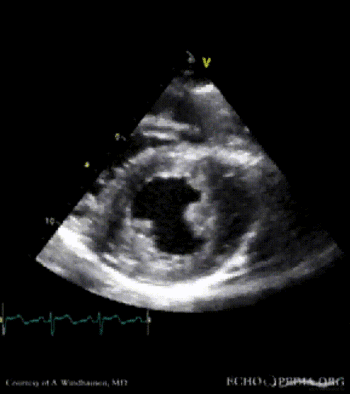

Severe Hypertrophic Cardiomyopathy (HCM)

Case description: Severe Hypertrophic Cardiomyopathy (HCM)

Courtesy of: A. Windhausen, AMC, The Netherlands

A2CH view A4CH view